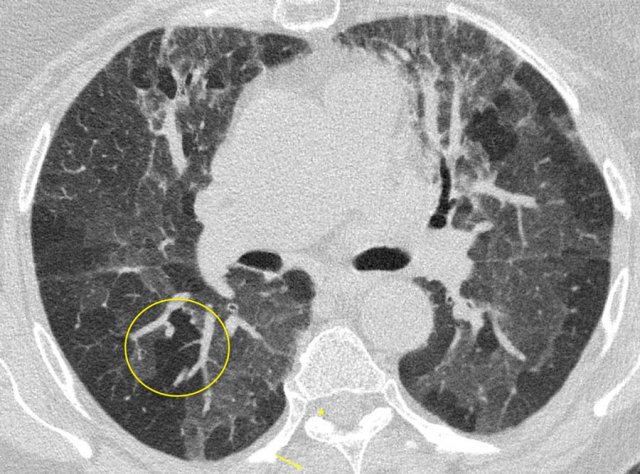

Ground glass opacities in hypersensitivity pneumonitis (HP) are also bilateral, but show a more geographical pattern.

In addition, HP has other features uncommon in COVID-19:

- Centrilobular nodules

- Headcheese sign” with a mixture of lobules with ground glass, normal density parenchyma, and air trapping

- Clinical presentation with a history of exposure to sometimes unknown antigens

- HP patients can develop fibrotic changes in a later stage.

The image shows typical bilateral groundglass opacities in hypersensitivity pneumonitis with head cheese sign: a mixture of ground glass, normal density parenchyma and air trapping (circle).